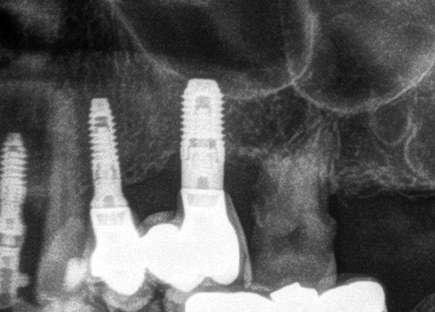

El tiempo de seguimiento fue de 112 meses +/14,85, no observándose ningún fracaso de los implantes estudiados durante este periodo. La media de la pérdida ósea mesial de los implantes estudiados fue de 0,15 mm +/- 0,71 , mientras que la distal fue de 0,31 mm +/- 0,69. Si estudiamos la pérdida ósea crestal separada entre los implantes atornillados y cementados obtenemos que para los implantes cementados la pérdida ósea distal fue de 0,47 mm +/- 0,80 y para los atornillados de 0,15 +/- 0,59 mm siendo las diferencias entre ambos grupos para la pérdida ósea distal estadísticamente significativas (p=0,03). En cambio, para la pérdida ósea mesial, no existieron diferencias estadísticamente significativas para los implantes atornillados y cementados, siendo la media de la pérdida ósea para los cementados de 0,27 +/- 0,83 y para los atornillados de 0,10 +/- 0,60. En la pérdida ósea de conjunto (media de la mesial y distal) para los grupos atornillado y cementado no existieron tampoco diferencias óseas significativas. En las figuras 3-10 se muestran imágenes de dos de los casos incluidos en el estudio.

Figuras 3-6. Imágenes de un caso de prótesis atornillada en molar unitario inferior. Vemos el estado de los tejidos blandos gingivales tras la segunda fase y colocación del transepitelial unitario y la radiografía. En las imágenes inferiores (5 y 6) observamos el caso a los 4 años y 10 años de seguimiento, con estabilidad completa de los tejidos óseos peri-implantarios.

Figuras 7-10. En las dos imágenes superiores (7 y 8) observamos la realización de la prótesis cementada mediante un bioplilar fresado a la altura gingival con la radiografía antes del cementado de la corona. En las imágenes inferiores (9 y 10) vemos la prótesis a los 7 años de seguimiento y a los 9 años transformada en una prótesis atornillada al perderse la pieza anterior al implante y realizarse un puente con el nuevo implante. En este caso, el nivel óseo permanece estable con el paso del tiempo.